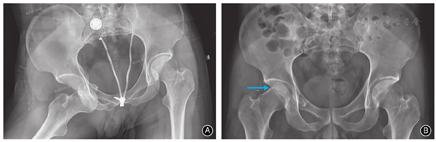

男,28岁,快递员。因骑电动车撞击花坛致伤2 h入院。急诊体格检查:右髋部疼痛、右下肢外展外旋畸形伴活动受限,远端肢体感觉及循环可。急诊摄骨盆正位X线片示右髋关节前脱位,股骨头塌陷(图1A);即行髋关节脱位手法闭合复位以避免股骨头脱位时间过长影响血供,复位后摄X线片证实右侧髋关节已复位(图1B)。骨盆CT示患者右侧股骨头外前象限压缩(图2);三维重建示股骨头塌陷约2.5 cm×3.0 cm,压缩体积略大于股骨头体积的10%(图3)。